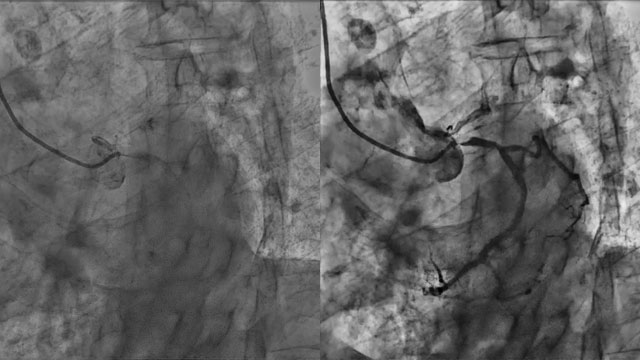

PCI for complex calcific coronary artery disease - LIVE Case

An 87-year-old female patient, at high bleeding risk and with preserved LV function, presented 2 months ago with an inferior STEMI and multivessel disease. She initially underwent RCA PCI followed by staged LCx PCI. She was now referred for PCI of a long, heavily calcified lesion...